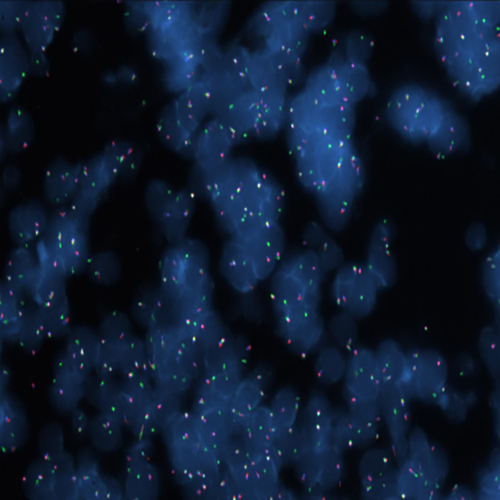

Hybridization of MYC TC break probe to a tissue section showing abarrant pattern (1GBR1G1BR).

IVD MYC (8q24) Break (tissue)

Rearrangements of the proto oncogene MYC c-myc) have been consistently found in Burkitt's lymphoma tumor cells. In cases with the common t(8;14) chromosomal translocation, the MYC gene is translocated to chromosome 14 and rearranged with the immunoglobulin heavy chain genes; the breakpoint occurs 5' to the MYC gene and may disrupt the gene itself. In Burkitt's lymphoma showing the variant t(2;8) or t(8;22) translocations, the genes coding for the k and l immunoglobulin light chain are translocated to v-myc avian myelocytomatosis viral oncogene homolog (MYC or c-myc) chromosome 8. The MYC (8q24) Break probe is optimized to detect rearrangements involving the 8q24 locus in a triple-color, split assay on formalin fixed paraffin embedded tissue.

MYC (8q24) Triple-Color, Break (tissue)